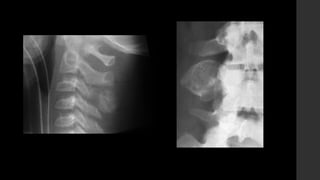

Osteoblastoma.

• RX 

Lesiones predominantemente líticas con un anillo esclerótico

reactivo periférico.

Tendencia a ser expansivas.

Presencia de calcificaciones internas.

Puede presentar masa de tejidos blandos asociada.

Tienen crecimiento rápido demostrado por expansión cortical,

algunas veces con destrucción cortical.

Puede presentar quiste óseo aneurismático en 20%.

• TC 

 Lesiones predominantemente líticas similares a la radiografía.

 La matriz interna se demuestra mejor en TC.